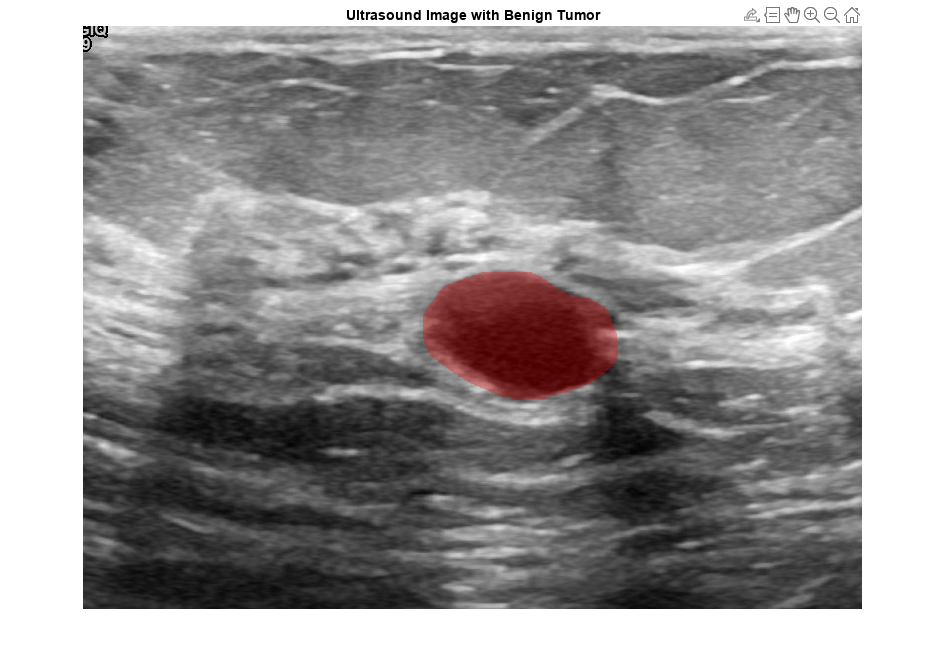

View an ultrasound image that contains a benign tumor with the tumor mask on the image.

benignIdx = find(imgds.Labels == "benign"); benignImage = readimage(imgds,benignIdx(146)); benignMask = readimage(maskds,benignIdx(146)); B = labeloverlay(benignImage,benignMask,Transparency=0.7,Colormap="hsv"); figure imshow(B) title("Ultrasound Image with Benign Tumor")